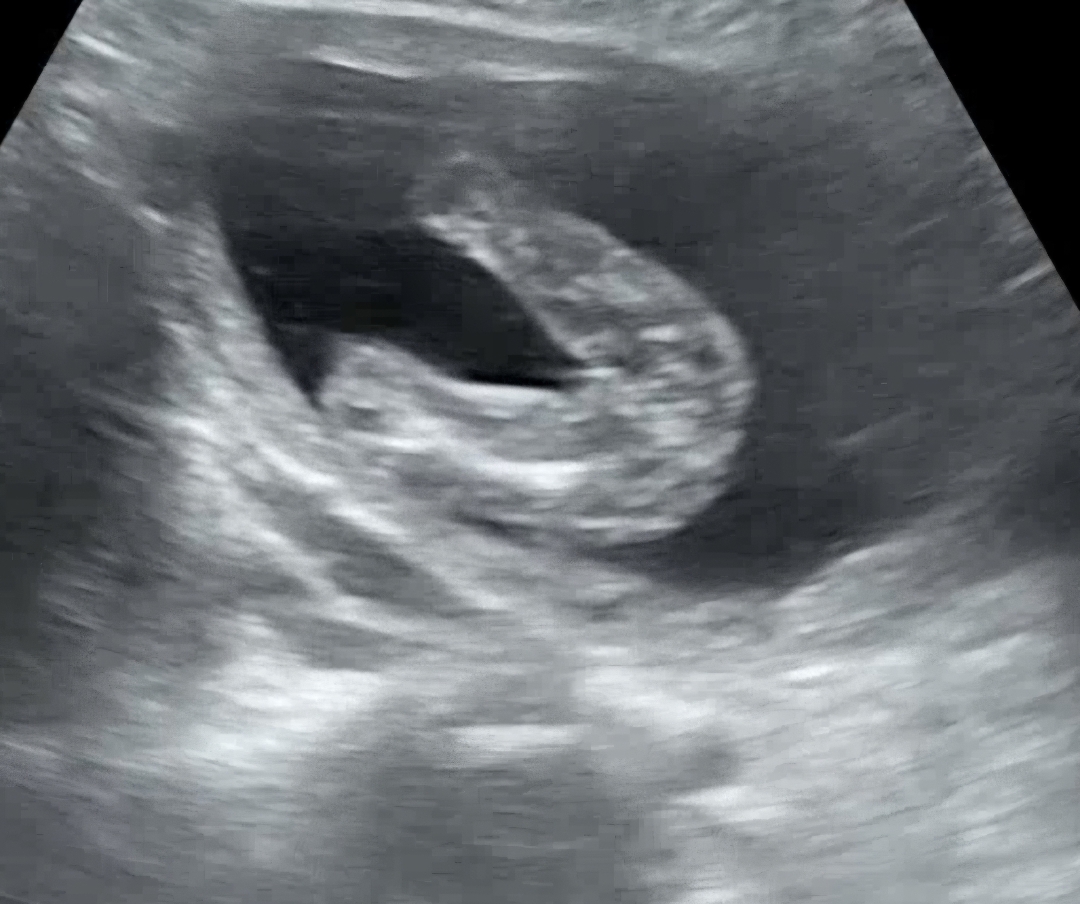

16주차 성별

젠더리빌 하려고하는데, 16주차 성별이 반전없겠죠?? 원장님께선 딸이네 한마디 해주셨어요 ㅎㅎ